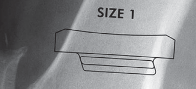

القوالب المسبقة (Preoperative Templating):

يتم استخدام الأشعة السينية لتحديد حجم وموضع المكونات المزروعة بدقة قبل الجراحة.